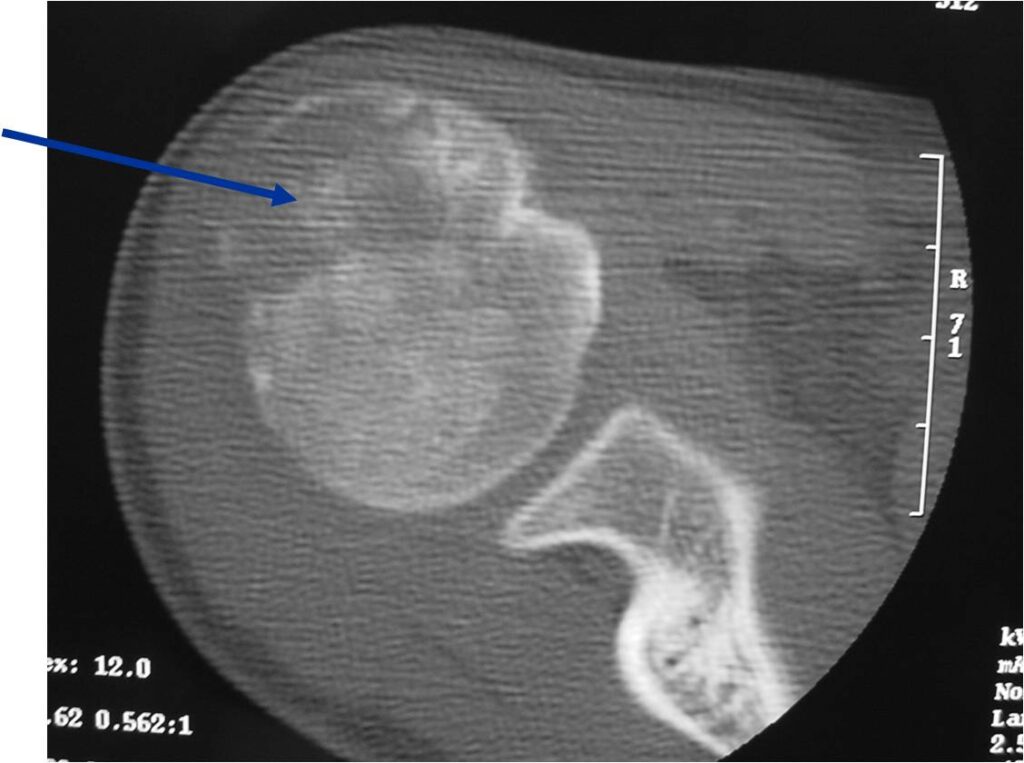

General Information Enchondroma is a benign indolent intramedullary hyaline cartilage neoplasm Accounts for 10% of all benign osseous tumors Limited growth, most lesions are less than 5 cm in maximal dimension Bones grow from a cartilaginous growth plate that...